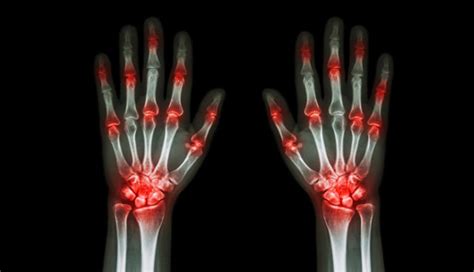

Apr 9, 2025 · When you have rheumatoid arthritis, your immune system sends antibodies to the synovium and causes inflammation. This causes pain and joint damage, especially in small joints in the fingers and …